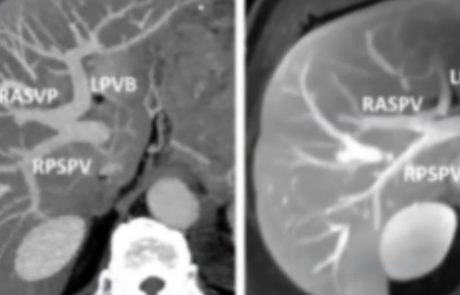

PV ANATOMY & APPROACH

As standard anatomy can only be observed in about 30% of patients, we need to assess the case at hand before performing a portography. The picture shows an example of Type 3 or “Z” anomaly, where the left PV and the right anterior PV share a common trunk. If we approach the procedure with this information we can plan a selective categorization of the branches and perform a fast and safe embolization using glue, as in this case. In order to reduce the risk of later FLR-related problems such as thrombosis, dissection, or hematoma, we usually prefer ipsilateral access, however, studies have shown that a contralateral approach presents a similar kind and rate of possible complications. At any rate, it is very important to avoid lesions, to reduce the risk of dissemination and subcapsular hematoma.

A safe puncture technique is extremely important: we use ultrasound guidance with a 21/22 gauge Chiba needle to puncture a peripheral PV (usually segment 5/6), then we place a 4/5 Fr vascular sheath and proceed to do a preliminary portography before we advance our diagnostic catheter. Multiple projections (anterior, posterior, oblique) are needed to confirm vascular anatomy and plan the embolization, which must include the branches of S4 whenever surgical planning involves its resection. Cone-beam CT is also an option: the anatomic details are excellent and we can obtain a volumetric 3D reconstruction. After thorough and correct planning, we can proceed to select the vessels and insert a coaxial catheter. Another option is to exploit the venous flow to treat multiple branches at the same time.